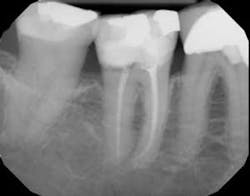

Each instrument and its accompanying technique have their own advantages and disadvantages. The key is to find a system to use in which all of the components are made to work together synergistically, such that they result in a procedure that is easy for the dentist to achieve the desired end results. In this instance, the desired end result is a debrided, clean canal that has been enlarged, shaped, and finished to receive a gutta-percha and sealed obturation (figures 1–4). This should be able to be achieved in an easy, quick, not too expensive, predictable, operator friendly manner. The dentist should not have to be Michelangelo to achieve the desired result consistently on every patient.